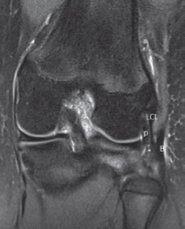

- Le muscle poplité est profond à la face postérieure du tibia (Fig. 2).

- La jonction myotendineuse se fait souvent par deux lames tendineuses convergentes (Fig. 3). Ces dernières seront vues au mieux sur des coupes coronales. Puis, le tendon rejoint la fossette du poplité (Fig. 4), au bord latéral du condyle, en passant dans le hiatus poplité puis sous le ligament arqué (Fig. 5).

- Les faces supérieure et inférieure du hiatus poplité sont constituées par les ligaments ménisco-poplités supérieur et inférieur. Le tendon du poplité est lié à la fibula par le ligament poplitéo-fibulaire (Fig. 6).